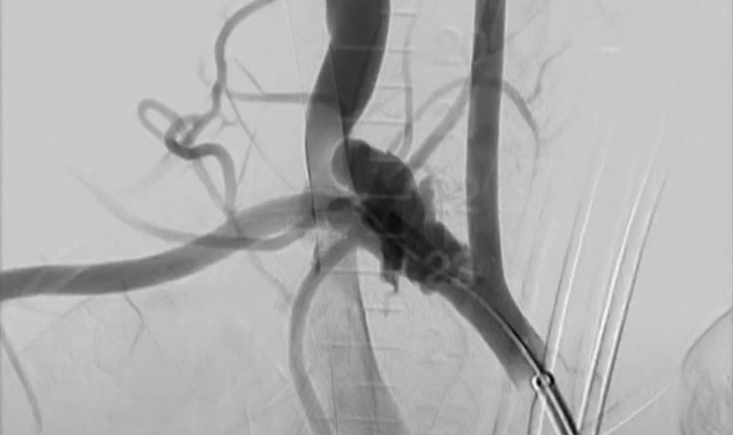

A significant part of the session is also dedicated to type 2 endoleaks, addressing both established and emerging approaches. Direct puncture versus transarterial strategies, the use of liquid embolics, and new polymer filling technologies are discussed through examples of what works—and what does not.

The session also tackles the ongoing debate on whether some type 2 endoleaks should be treated endovascularly or managed through surgical conversion.